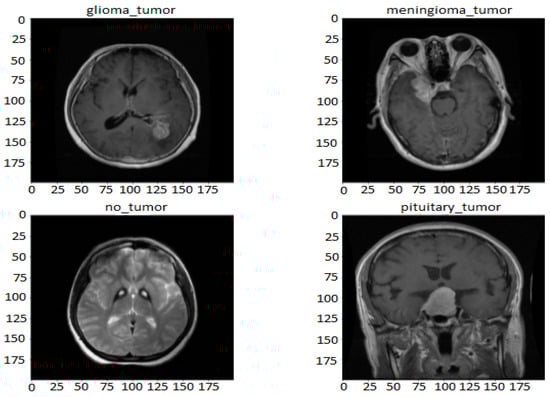

3.1. Dataset